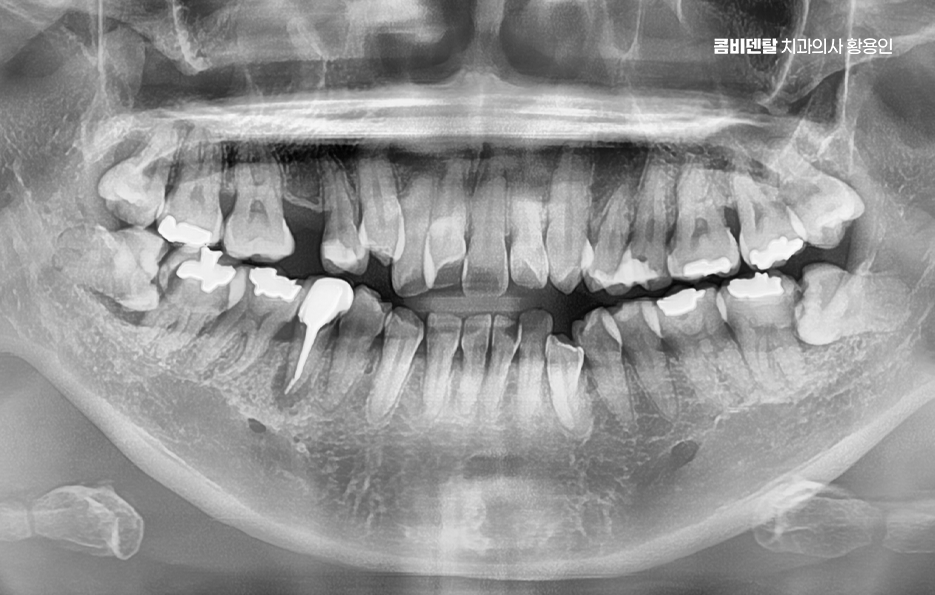

출처 아카이브 열기거울을 보다 보면 늘 시선이 먼저 가는 게 앞니였어요, 남들이 보기엔 별로 티 안 나는 거라고 생각하기도 했지만 항상 앞니가 조금 틀어져 있다는 걸 의식하게 됐고, 사진 찍을 때도 살짝 미소만 짓게 되는 이유가 그거였어요, 사실 예전부터 교정을 해야겠다는 생각은 있었지만 앞니만 살짝 신경 쓰이는 정도라서 큰 결심까지는 안 갔었고, 그냥 참고 살면 되지 뭐 이런 식으로 넘기곤 했는데, 어느 날 치과에 전반적인 치열이 생각보다 안 좋은 편이라고 말씀하시는 걸 듣고는 좀 충격을 받았어요, 제 눈에는 앞니만 문제였지 전체적인 교합이 그렇게 문제인 줄은 몰랐거든요. 정확한 상태를 알기 위해 정밀 검사를 받았는데, 앞니가 살짝 겹쳐 있는 건 물론이고 아래쪽 어금니는 바깥쪽으로 기울어져 있어서 씹는 힘이 한쪽으로만 가고 있고, 전반적으로 치아 배열이 삐뚤빼뚤하게 늘어선 상태라 기능적인 문제도 고민할 수 밖에 없었어요

전체적인 부정교합을 교정하려면 먼저 교합 상태, 즉 위아래 치아가 어떻게 맞물리는지를 확인해야 하는데 위턱과 아래턱이 서로 자연스럽게 맞물리지 않고, 삐뚤거나 앞니가 부딪치거나, 아래턱이 더 튀어나와 있는 경우가 많이 있었어요

또 턱의 비대칭이나 턱관절 이상이 있는지까지 함께 체크해야 하는데 이런 부분을 모두 포함해서 앞니 틀어짐 교정 치료 계획이 세워져야 하며 얼굴의 중심선과 턱의 위치까지 고려한 계획이 필요한 거예요.

앞니 틀어짐 교정 앞니가 많이 틀어져 있는 경우에 발치가 필요한 경우도 있는데 공간이 부족한 상태에서 억지로 밀어넣으면 교정은 되지만 얼굴형이 부자연스러워지거나, 입이 오히려 더 튀어나와 보일 수 있어서 위아래 소구치를 발치해서 공간을 만들고, 그 공간을 활용해 전체 치아를 재배열하는 방식이 흔히 사용되고 있어요

물론 발치 여부는 개인의 얼굴형, 입술 돌출 정도, 잇몸뼈 두께 등 다양한 요소를 고려해서 결정하는 것이며 비발치적인 방법인 치간삭제, 어금니 후방이동, 악궁확장과 같은 방법으로 치아 이동 공간을 확보하여 비발치 치아교정이 가능한 경우도 있었어요